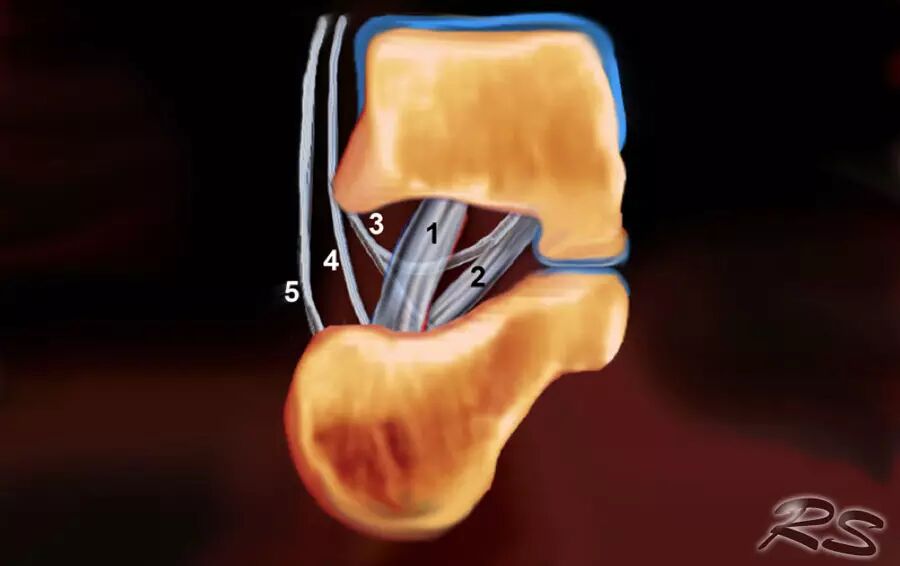

跗骨窦

跗骨窦是锥形空腔,在后内侧到前外侧方向上延伸。它位于距骨的颈部和跟骨的前上表面之间的脚的外侧面。跗骨窦内侧继续作为跗管,这是距骨与跟骨间一个漏斗形的空间。它包含脂肪,动脉吻合,关节囊,神经末梢和五个韧带结构 - 下伸肌视网膜的内侧,中间和侧根; 颈韧带; 和骨间骨骨膜韧带(图)。

这个空间可以是脚部疼痛在跗骨窦综合征的原因。治疗的第一步是用epomedrol和局部麻醉剂(利多卡因)的混合物封闭治疗。这对于外科医生在非引导方法中可能是挑战性的,但是用超声引导相当容易和准确地实现

超声引导的跗骨窦的注射在右手侧与外侧入路。探头保持在冠状倾斜平面中。针沿着探头的长轴引入。

使用超声波可以容易地观察窦性骨壁。患者转向对侧,将待治疗的足以其内侧表面靠在桌面上,脚的外侧位于最上面。探头保持在关于脚的冠状平面中。

在跗骨窦被识别为跟骨的前处理和距骨颈之间的三角空间。针(箭头)的前端的锥形跗骨窦,这是由距骨(T)和跟骨(C)的边界内可以看到。

根据炎症的程度,可能存在空间的充血,并且可能存在中间血管可见,这是人们希望避免的。但是这又是比较容易的,特别是彩色多普勒。